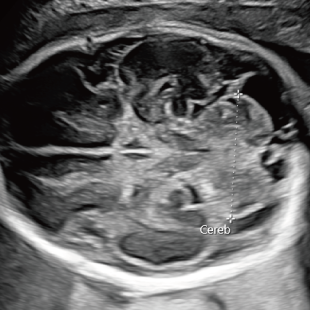

妊娠後期は、胎児の成長がさらに進み、発育の途中で現れてくる変化を確認できる時期です。中期の検査では問題が見られなかった場合でも、成長に伴って形態の変化が現れることがあります。また、構造だけではなく、胎児機能(赤ちゃんの元気度)の評価も可能となります。後期スクリーニングでは、各臓器の状態や構造に加え心臓の動きや血液の流れなどをより詳しく観察します。

胎児ドックの様子_後期_頭 胎児ドックの様子_後期_心臓 胎児ドックの様子_後期_心臓 胎児ドックの様子_後期_足 胎児ドックの様子_後期_4D